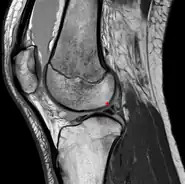

Posterior meniscofemoral ligament on MRI, coronal

Posterior meniscofemoral ligament on MRI, sagittal